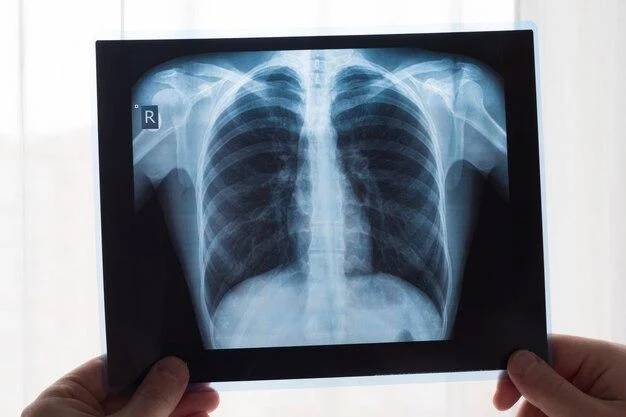

A chest X-ray is a sort of imaging examination that is commonly used to evaluate the heart, lungs, and chest wall. It might aid in the detection of diseases including pneumonia, lung cancer, collapsed lungs, and rib fractures.